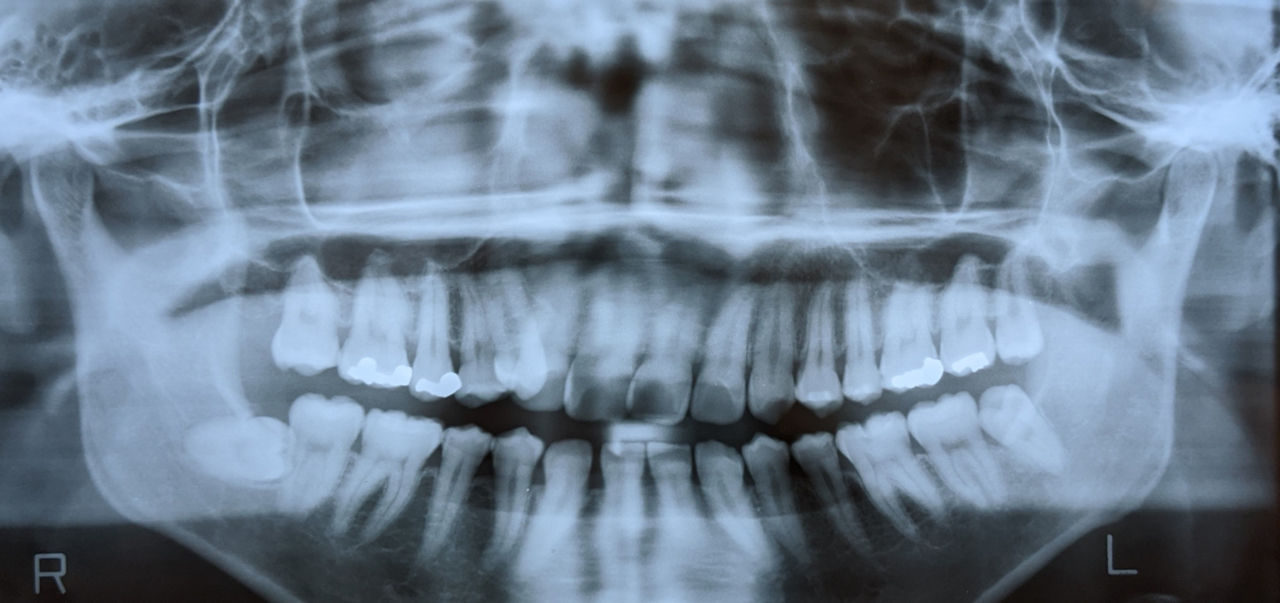

レントゲン撮影

インプラント治療は、あごの骨に人工歯根を埋め込む治療なので、あごの骨の状態を確認することも大切です。

ご希望の方には無料で、レントゲン検査も行います。

目に見えないあごの骨の様子がわかるため、

• インプラントができる状態なのか

• 他に必要な治療がないか

• 治療費や治療期間

といったことを、より詳細にご案内できます。

精密検査(CT)

CT撮影を行わない医院もあるのですが、当院では歯科用CTでの3次元診断も行っています。

2次元のレントゲンではわからない、骨の厚みや高さ、血管や神経の位置を見ながら診断することで、より安全正確な治療計画を立てられるからです。